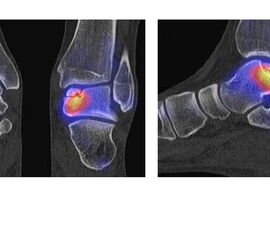

Abbildung 2.1.

Bildbeispiele symptomatische OCL

Zum Lesen der Bildbeschreibung und zur Vollansicht bitte das Bild anklicken. Bild: H. C. Rischke

Abbildung 2.2.

Bilder eines Patienten mit Z. n. mehrfachen Sprunggelenksdistorsionen in der Vergangenheit, besonders heftige Distorsion des linken Sprunggelenkes 5 Wochen vor der Untersuchung. Die SPECT/CT zeigt eine instabile osteochondrale Läsion mit deutlicher Aktivierung.

Abbildung 2.3.

Klärung bei Schmerzen im rechten OSG bei OCL an der medialen Talusschulter. Z. n. OSG-Distorsion vor 2 Jahren und Z. n. OSG-Fraktur / Syndesomosenruptur. Ausgedehnte OCL, hier jedoch kein erhöhter Knochenmetabolismus; lediglich Nachweis einer Stressreaktion im Bereich der Synchondrose eines Os trigonum als Schmerzursache.